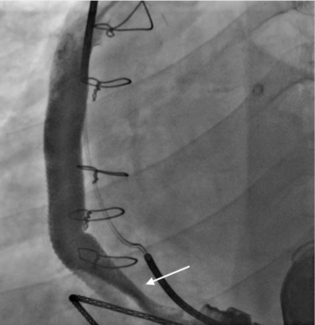

A 64-year-old female presented for closure of her left axillary access for intra-aortic balloon pump (IABP). We intended to close the access with standard balloon-assisted dry closure. A 7-Fr slender radial sheath was placed via left radial...